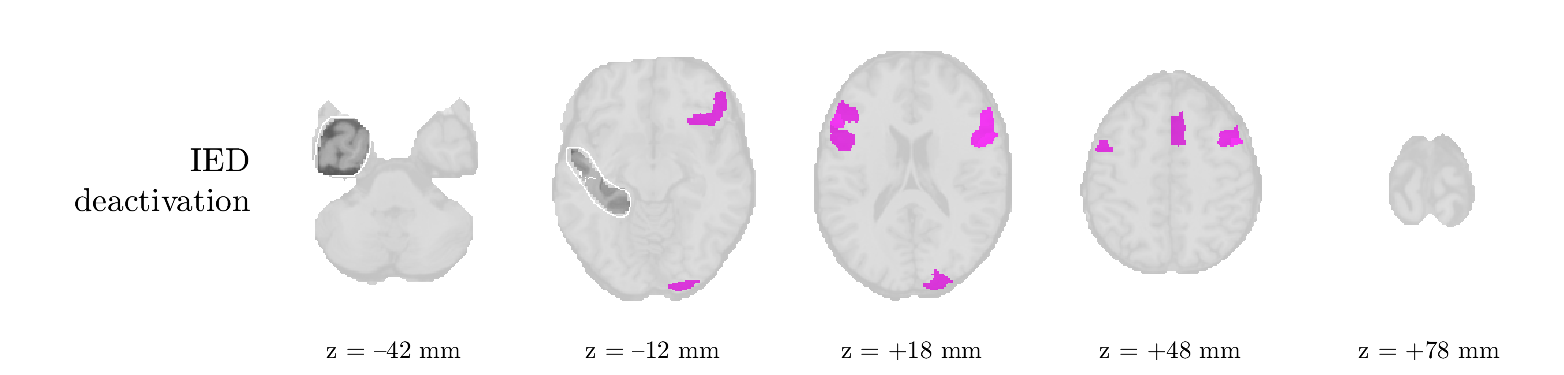

We analyze the solution with sources. Figure 1 shows the EEG signatures and HRF waveforms. One of the sources is highly correlated to the MWF reference (in grey), which was already known from Table B.3. This IED-related source had a typical low-frequency spectrum, which is expected for the typical spike-and-wave interictal discharges. The topography is relatively diffuse, although the highest amplitudes are mostly in the left hemisphere. This is in accordance with the lateralization of ictal onset zone (left temporal lobe, cfr. Table 1). There are some noteworthy observations to be made about some of the other components. The fourth has an unusually sharp spectrum, is mainly localized on two nonadjacent center electrodes, and is sustained for a single period of many seconds Hence, this component likely captured an artifact (of yet unknown origin), although we spotted no large-amplitude changes in the EEG itself. Similarly, the third source is only present at one frontal electrode, and exists in a frequency range above 20 Hz. It might represent a muscle artifact, e.g., due to frowning or twitching of some muscles in the forehead. The HRFs of all ROIs are shown in Figure 1(b). Two of the basis functions seem to have converged to a very similar waveform, which is an unfortunate possibility if two initial HRFs are too close to the same local optimum in their respective parameters. This reduces the expressive power of the basis set, which is clearly visible, since many ROIs have a nearly identical HRF. One of the twenty ROIs with the highest-entropy HRF overlapped the IOZ, although clearly this HRF (bold line) is not among the most dissimilar waveforms for this patient. This is also visible in Figure 2: both the HRF entropy and extremity maps show a small overlap with the delineated IOZ. Despite the good correspondence in the EEG domain, no significant (de)activation of the IED-component is found inside the IOZ.